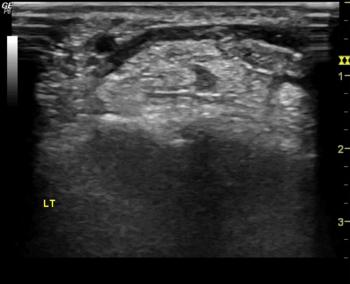

Figure 1. Ultrasound images depicting hydrodissection procedure in a patient with carpal tunnel syndrome. (A) Needle placed below the median nerve with fluid dissecting the nerve from the underlying flexor tendons (green star). (B) Needle placed above the median nerve with fluid dissecting the nerve away from the flexor retinaculum (yellow star). (C) Image at completion of procedure depicting the dissected median nerve with fluid all around. Red Arrow - needle, Blue cross -hydrodissection fluid, white dashed lines - median nerve.

High-res (TIF) version